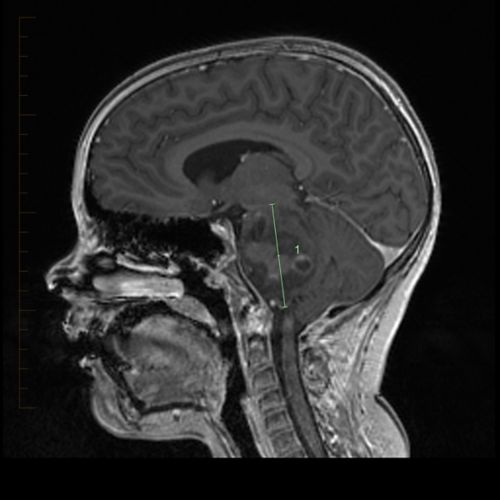

Dipg Tumor : Titiens Therapie: Die erste Verteidigungslinie bricht ... / Here, we review both dipg tumor cell's intrinsic molecular processes and extrinsic environmental while the acvr1 mutation is causal for fop, its role in dipg tumor biology remains under active.. , ionkin d.a., zhavoronkova o.i., vetsheva n.n., shurakova a.b., bugaev s.a., kungurtsev c.v. Dipg brain tumour is an aggressive form of childhood brain cancer. A diffuse intrinsic pontine glioma (dipg) is a tumour located in the pons (middle) of the brain stem. Dipg is a brainstem glioma. Diffuse midline gliomas (previously called dipg brain tumours) grow in the areas of the brain that are found in the midline, this is the natural centre line of the brain between its two halves.

In the united states, approximately 300. Dipg is a brainstem glioma. The diagnosis of dipg is based on radiographic findings in the setting of a typical clinical presentation, and tissue is not routinely obtained as the standard of care. Glioma is a general name for any tumour that arises from the supportive tissue called glia, which help keep the neurons in place and functioning well. Retinal vascular tumors / nikolaos e. A diffuse intrinsic pontine glioma (dipg) is a tumour located in the pons (middle) of the brain stem. Dipg brain tumour is an aggressive form of childhood brain cancer. Dipg tumor is considered as a childhood tumor and almost 10 percent of central nervous system related childhood tumors are estimated as dipg tumor. A, b note the highlighted tumor burden in individual. Dipg brain tumors are most common in children ages 7 to 9, but it. Tumor volumes were computed with additive roi's from each slice using flair imaging. Cryoablationin patients with unresectable liver and pancreatic tumors. Dipg is a logical tumor for using ced, since it is constrained within a limited anatomical children with a clinical and radiographic diagnosis of nonprogressive dipg who have received standard.

Dipg tumor is considered as a childhood tumor and almost 10 percent of central nervous system related childhood tumors are estimated as dipg tumor. A diffuse intrinsic pontine glioma (dipg) is a tumour located in the pons (middle) of the brain stem. Dipg is a logical tumor for using ced, since it is constrained within a limited anatomical children with a clinical and radiographic diagnosis of nonprogressive dipg who have received standard. Cryoablationin patients with unresectable liver and pancreatic tumors. Diffuse intrinsic pontine gliomas (dipg) are highly aggressive and difficult to treat brain tumors found at the base of the brain.